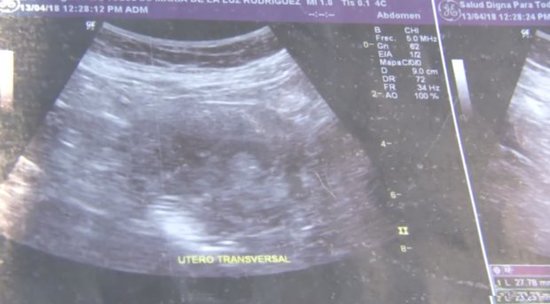

Meksikanın Sinaloa ştatının Masatlan şəhərinin sakini Mariya de la Luz 6 aylıq hamilə olduğunu bildirir.

Ariya Ultrasəs müayinəsindən keçib və qız övladı dünyaya gətirəcək.

Bundan sonra isə ultrasəs müayinədən keçib. İlk müayinədən sonra Mariya gözlərinə inanmayıb və 10 başqa klinikada da müayinədən keçib. Bütün klinikalar qadının hamilə olduğunu deyib.